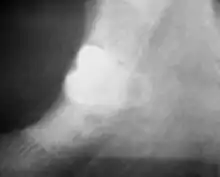

| 3D CT of an impacted wisdom tooth adjacent the inferior alveolar nerve prior to removal of wisdom tooth | |